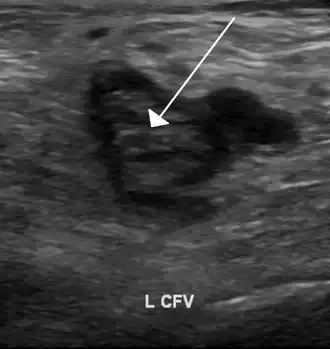

-

An ultrasound with a blood clot visible in the left common femoral vein. (The common femoral vein is distal to the external iliac vein.)

Compression ultrasonography for suspected deep vein thrombosis is the standard diagnostic method, and it is highly sensitive for detecting an initial DVT.[118] A compression ultrasound is considered positive when the vein walls of normally compressible veins do not collapse under gentle pressure.[39] Clot visualization is sometimes possible, but is not required.[119] Three compression ultrasound scanning techniques can be used, with two of the three methods requiring a second ultrasound some days later to rule out the diagnosis.[118] Whole-leg ultrasound is the option that does not require a repeat ultrasound,[118] but proximal compression ultrasound is frequently used because distal DVT is only rarely clinically significant.[117] Ultrasound methods including duplex and color flow Doppler can be used to further characterize the clot[117] and Doppler ultrasound is especially helpful in the non-compressible iliac veins.[119]